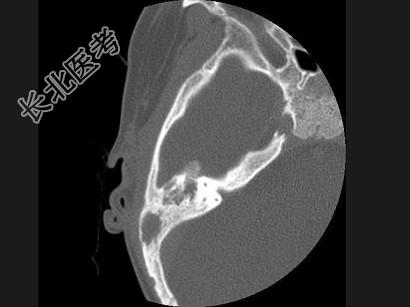

- 单项选择题女,17岁, 右耳乳突区隐痛,右耳后乳突区出现包块, 逐渐增大,CT检查如图, 最可能的诊断是 ( )

A、胆脂瘤

B、化脓性中耳炎

C、嗜酸性肉芽肿

D、中耳癌

E、听神经瘤